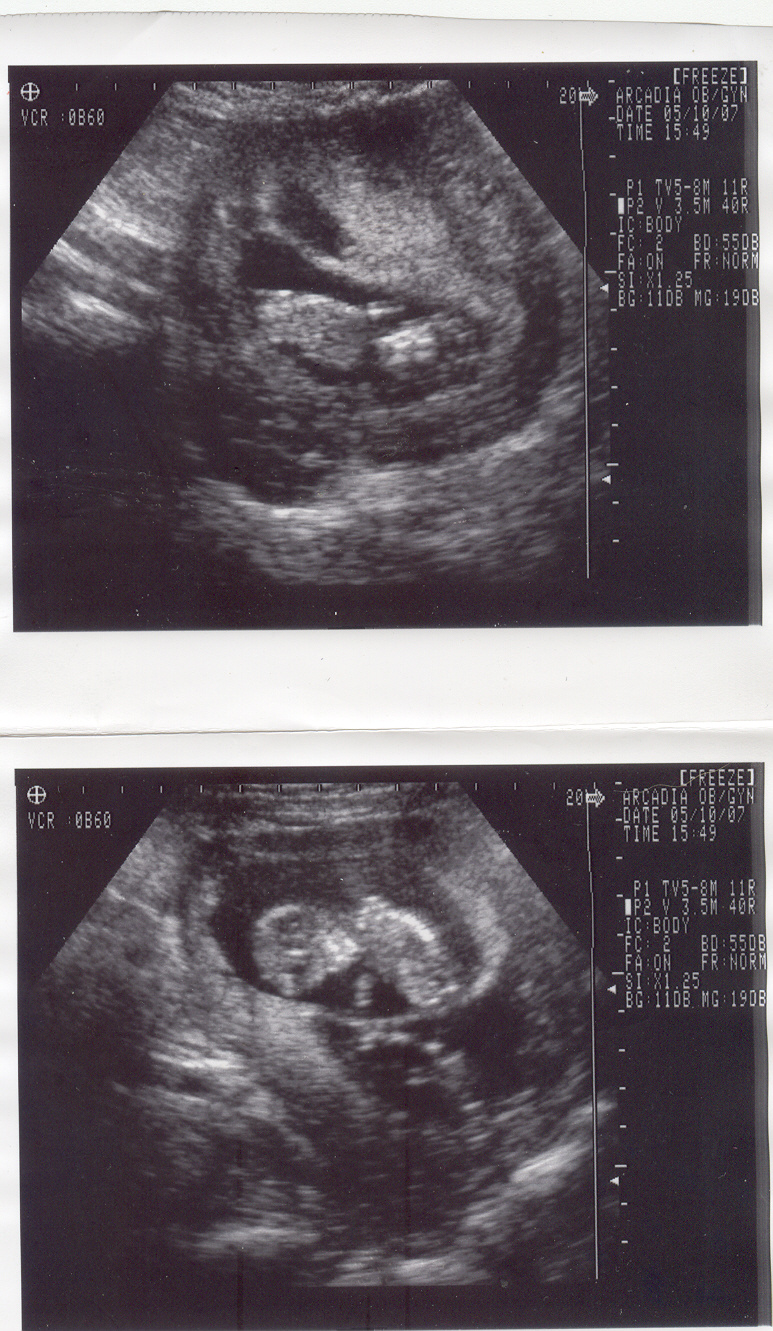

Our Daughter (Amanda is pregnant with twins we know one is a boy my first Grandson I am just beside myself about this the 2nd baby we do not know weather it is a boy or girl because of its position but both baby's are very healthy. Although Amanda is having some difficulty's in the last week that the Doctor put her on a months bed rest. Well with that she has a very rambunctious 2 year old so I/We have been going over and helping with our first Grand baby On my way home from work I stop by and play with her and get her tired so she do's not bug Mom.

In the Pic the lower baby is the boy he is the one that is pushing on Mama's uruis wall causing the bleeding.

Twins@6_weeks.jpg

Twin Grand baby's